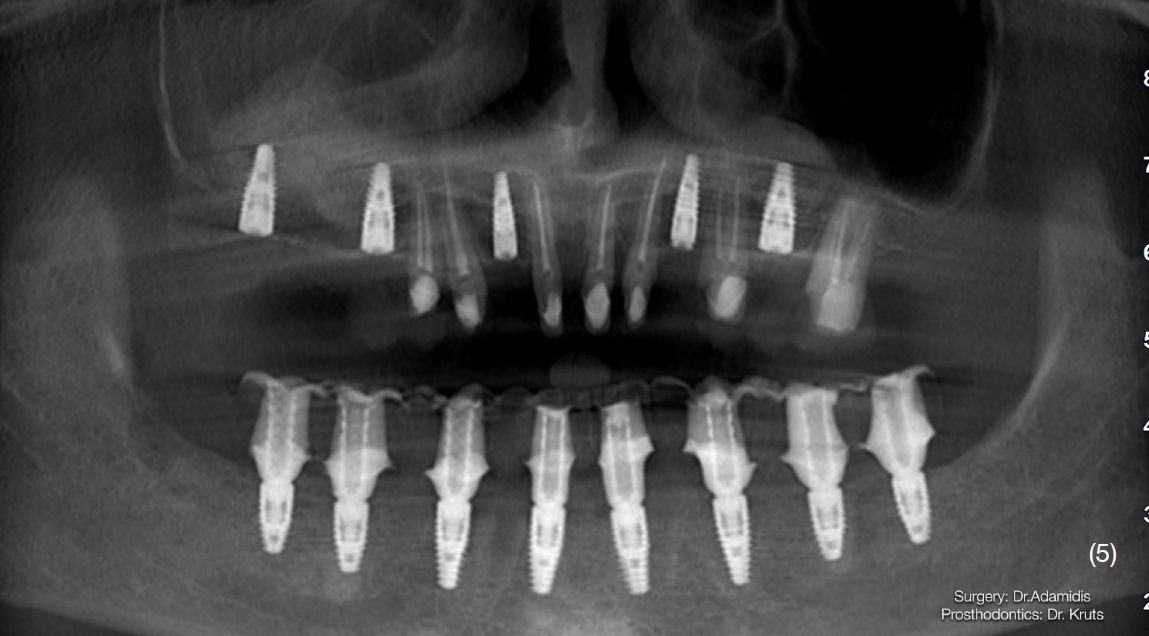

Після детального вивчення даних комп’ютерної томографії пацієнта, було затверджено план лікування, який складався із двох хірургічних етапів.

Етап 1. Робота з нижньою щелепою:

Екстракція наявних зубів та одномоментне встановлення 8 імплантатів Straumann BLT з використанням навігаційного хірургічного шаблону. В це ж відвідування було зафіксовано тимчасову конструкцію з рівня імплантатів, без використання мультиюніт-абатментів. Станом на цей момент для тимчасової реабілітації верхньої щелепи вже було виготовлено та зафіксовано провізорну конструкцію з опорою на зуби.

Через 3 місяці після першого етапу було проведено операцію на верхній щелепі. Було виконано відкритий синус-ліфтинг в першому квадранті та закритого в другому.

Одномоментно з кістковою аугментацією встановлено імплантати Strauman BLT діаметром 3.3mm в ділянках 12, 15, 17, 23, 25 зубів. Операційну рану було ушито, зворотньо зафіксовано тимчасову конструкцію на наявних зубах.

Верхню щелепу реабілітовано коронками з опорою на зуби та імплантати.